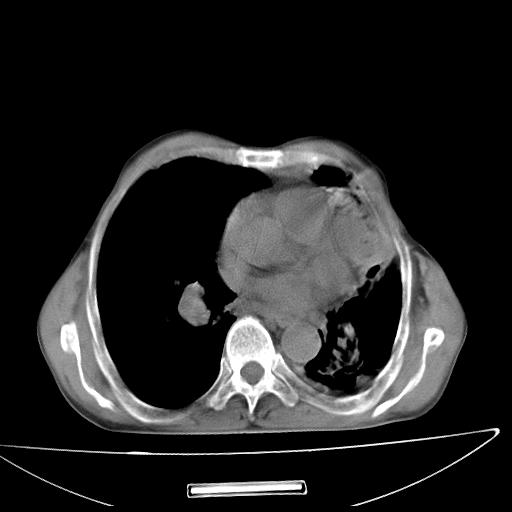

男  70岁,发烧咳嗽4天。盗汗,消瘦。无痰中带血丝,以前有肺tb病史,ct见,双肺tb,左侧胸廓塌陷,左胸膜肥厚粘连。纵隔移位,右侧胸腔积液,大家说说那个心影前左肺舌叶除了肺大炮还有炎症还是干酪性肺炎?有占位吗?我看纵隔淋巴结也大。

是胃,纵膈未见明显肿大淋巴结。

1)两肺继发性肺结核并左肺上叶肺不张,支气管扩张。2)双侧胸膜炎(胸膜增厚+少量胸腔积液)。